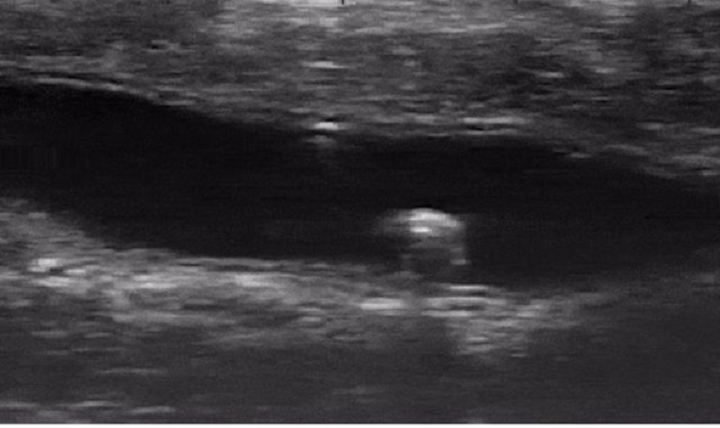

Con robot nhỏ tới mức không thể mang theo pin. Thay vào đó, nó được cấp nguồn và điều khiển từ bên ngoài nhờ từ trường. Nhờ hình ảnh siêu âm, nhóm nghiên cứu có thể theo dõi chuyển động của nó từ bên ngoài ruột kết.

Con robot hình chữ nhật chứng minh nó có thể điều hướng thành công trên các bề mặt khô và ướt, bẳng phẳng hoặc gồ ghề. Hành động nhào lộn của nó được thiết kế đặc biệt để có thể di chuyển tới các khu vực khó quan sát bên trong ruột động vật.